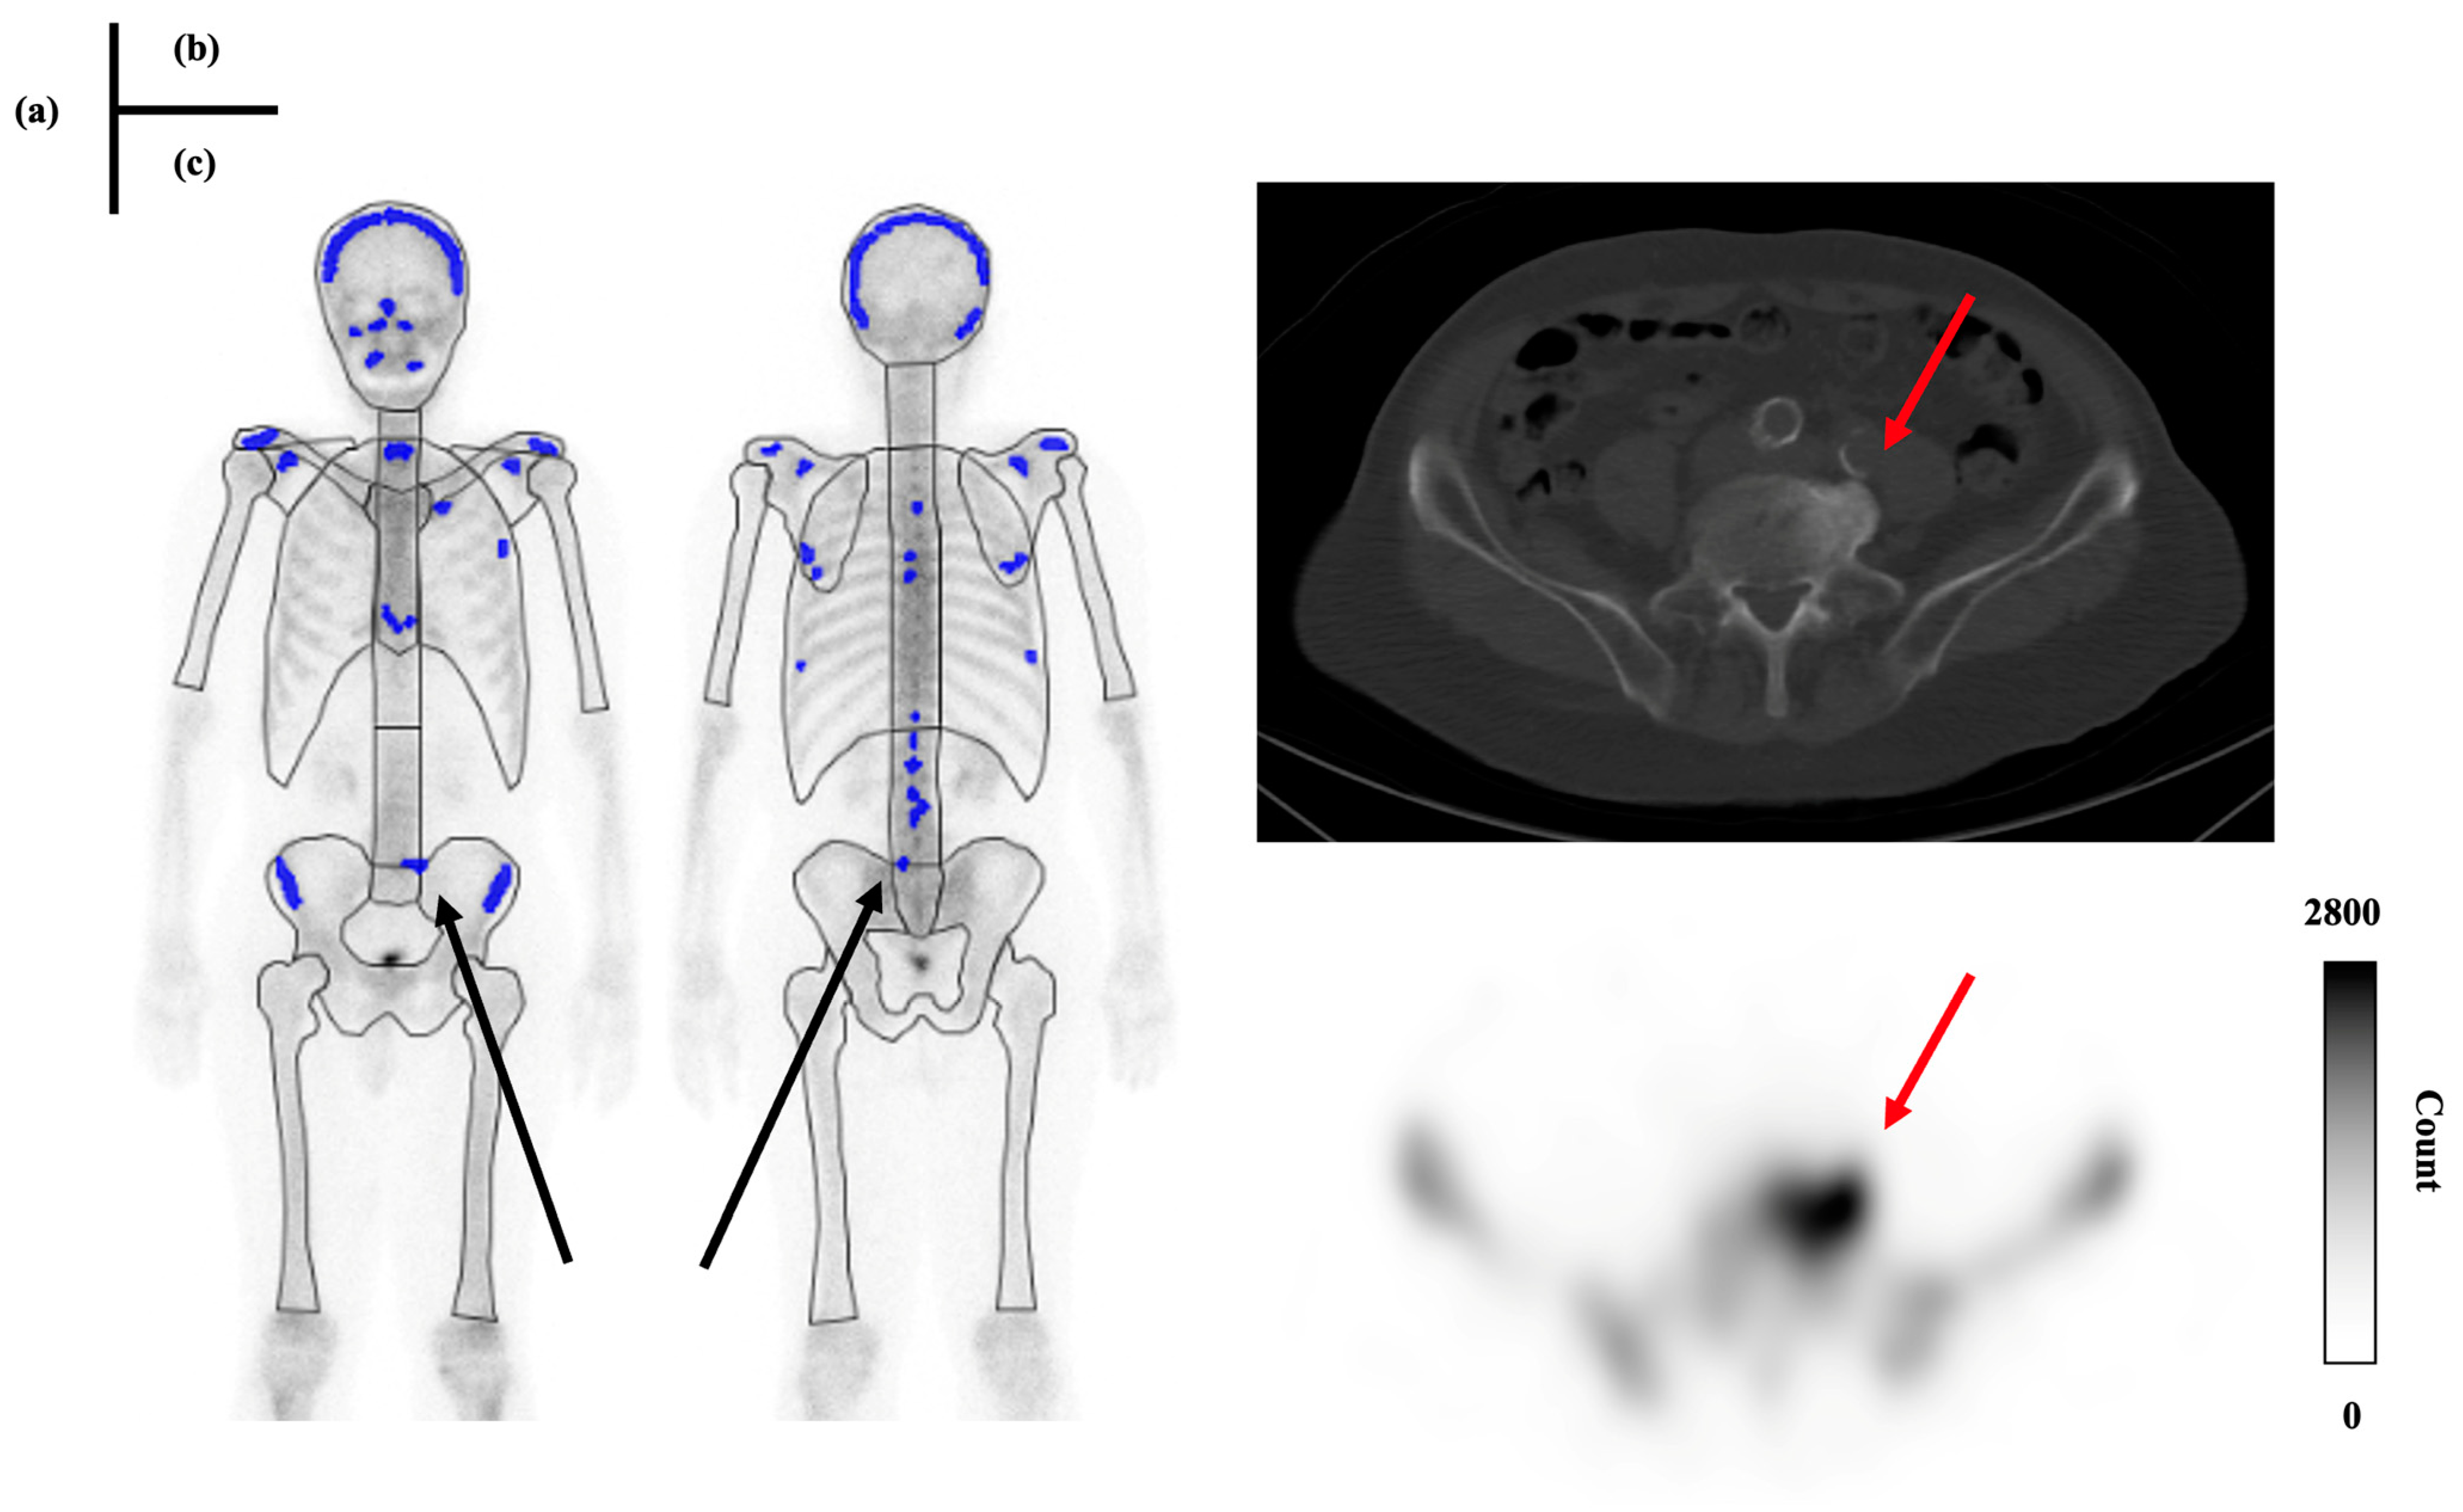

2.3. Imaging

2.4. Criteria for the Presence or Absence of Bone Metastasis

2.5. Case Grouping and Data Analysis